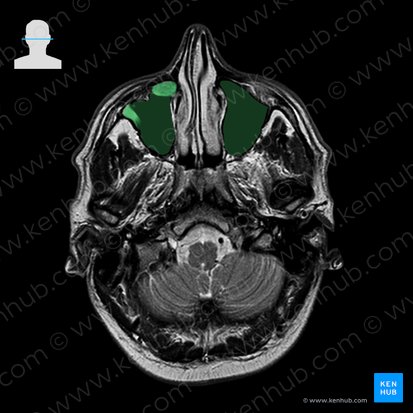

Nasennebenhöhlen (Sinus paranasales)

Die mit Schleimhaut ausgekleideten Nasennebenhöhlen zählen zu den sogenannten lufthaltigen Knochen, den Ossa pneumatia, die beim Menschen ausschließlich am Schädel zu finden sind.

Sie stehen mit der Haupthöhle der Nase in Verbindung und dienen so der Befeuchtung und Anwärmung der Atemluft, sowie als Resonanz- und Klangkörper zur Sprachbildung.

| Sinus maxillaris (Kieferhöhle) | Liegt im Corpus der Maxilla; Besitzt ein Volumen von etwa 12-15 cm³ |

| Cellulae ethmoidales (Siebbeinzellen) | 2 - 10 größere Cellulae ethmoidales anteriores und 2 - 6 kleinere Cellulae ethmoidales posteriores |

| Sinus frontalis (Stirnhöhle) | Liegt in der Pars nasalis des Os frontale; Vier Formvarianten: Blattform, Bohnenform, Mitralform (am häufigsten) und Pyramidenform |

| Sinus sphenoidalis (Keilbeinhöhle) | Liegt paarig im Os sphenoidale vor; Grenzt nach oben an die Sella turcica (Türkensattel) und an die vordere und mittlere Schädelgrube |

Unter dem Begriff Siebbeinlabyrinth werden alle 8 bis 15 Siebbeinzellen zusammengefasst, die zwischen oberer Nasenhöhle und Orbita liegen. Dazu zählen 2 bis 10 größere Cellulae ethmoidales anteriores und 2 bis 6 kleinere Cellulae ethmoidales posteriores.